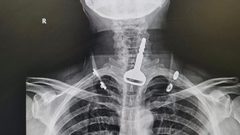

جراح سعودي ينقذ حياة أربعيني ابتلع مفتاح سيارته